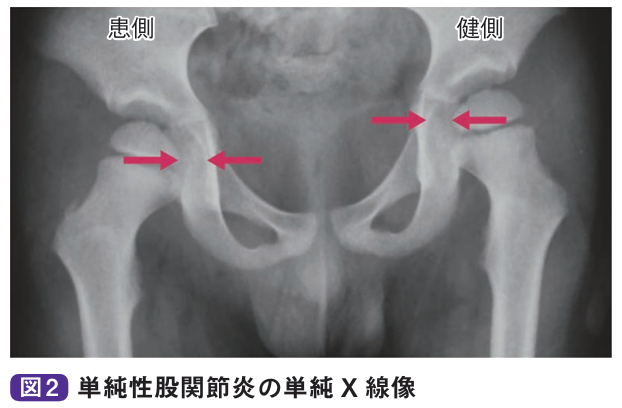

単純性股関節炎は小児の股関節痛のもっとも多い原因疾患です。一過性の滑膜炎で、通常1-2週間程度の経過観察あるいは安静で軽快することがあります。好発年齢は3〜10歳で、男児に多く発症します。通常は片側に発症し、両側同時発症や多関節発症例はありません。おもな症状は股関節痛ですが、股関節痛以外にも大腿や膝の痛みを訴えることがあります。ウイルス感染や溶連菌感染との関連が考えられているほか、外傷説、アレルギー説などがありますが、原因ははっきりとは解明されていません。

診察とレントゲン、エコーなどで診断します。関節可動域は軽-中等度と制限され、とくに屈曲位で内旋が制限されます。微熱を認めることがありますが、通常、血液所見は正常値を示します。単純X線像では関節液の貯留により関節包陰影の膨隆、関節裂隙(れつげき)の開大、骨頭の外方化などを認めますが、骨陰影に異常を認めません。超音波検査やMRI検査で関節液貯留が明らかとなります。